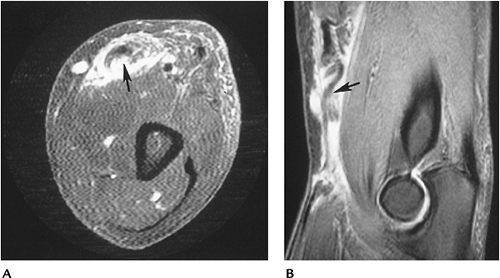

![]() |

FIGURE 8-20 Biceps tendon tear. Axial (A) and sagittal (B) T2-weighted images of a biceps tendon tear (arrow) with retraction and surrounding hemorrhage and edema.